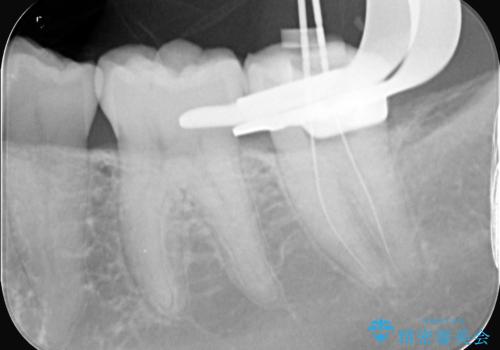

- 昨日からのズキズキとした激しい痛みを主訴にご来院されました。レントゲンおよび歯髄診察の結果、不可逆性の歯髄炎(歯の神経の重度の炎症)と診断。歯を残すことを第一に、まず痛みの原因である神経を取り除く根管治療を提案しました。また、虫歯が歯肉の下まで深く進行していたため、根管治療後に歯周外科処置を行い、最終的に精密なセラミッククラウンで修復する、総合的な治療計画を立案しました。

治療はまず、根管治療から始め、感染した神経を徹底的に除去することで、痛みをすぐに解消しました。再発を防ぐため、ラバーダムや顕微鏡を使って、根管内を丁寧に、そして精密に処置しました。次に、深い部分の虫歯を確実に治療するため、歯周外科処置を行い、治療しやすい環境を整えました。最後に、機能と見た目に優れたセラミッククラウンを作製・装着。根管治療から外科処置、審美修復までを一貫して行うことで、再発リスクの低い、長期的に安定して使える奥歯を取り戻していただけました。